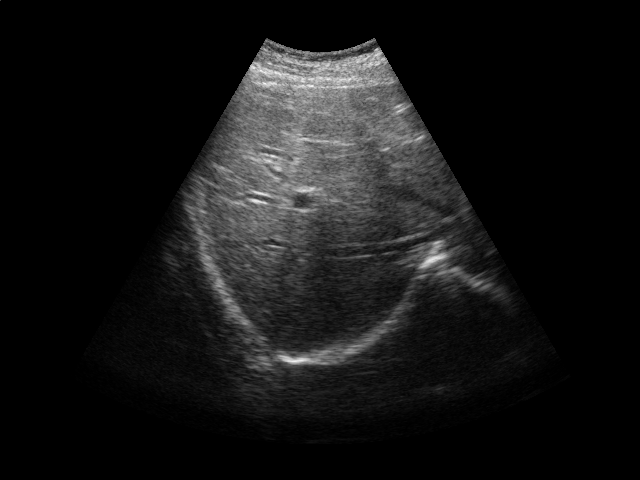

Refer to caption

Figure 2: Ultrasound gating. Top: Ultrasound images of the liver over time (abdomen, right upper quadrant). Bottom left: Correlation coefficient vs. error tolerance ε𝜀\varepsilon. Bottom right: The number of support vectors vs. error tolerance ε𝜀\varepsilon. Both figures in the bottom report results for different values of kernel ridge regression regularization parameter λ𝜆\lambda.

Respiratory gating tracks a patient’s breathing cycle, which has numerous applications such as 4D imaging, radiation therapy, and image mosaicing [16]. Manifold learning has been used for highly accurate respiratory gating of ultrasound images [23], where 4D data reconstruction was achieved with retrospective gating, i.e., the gating was calculated after the data acquisition was finished. We extend this work to attain real-time gating. A small number of breathing cycles are acquired and used as input for manifold learning to construct the respiratory signal, as is done for retrospective gating. The new incoming stream of ultrasound images is then gated by performing an out-of-sample extension.

We conduct experiments on five 2D ultrasound image sequences of the human liver acquired during free breathing; example images are shown in Fig. 2. Each sequence contains 640×\times480-pixel images and vary in length between 298 and 371 frames captured at 33 Hz. For a given image sequence, we use each image in the sequence as an input data point for learning a 1D manifold with Laplacian eigenmaps [4]; we use a 9-nearest-neighbor graph with an associated heat kernel of temperature t=10𝑡10t=10. The 1D embedding learned using an entire sequence of images serves as a reference signal for evaluating our sparse out-of-sample extension versus kernel ridge regression as the baseline. In what follows, we compare the 1D embedding of our sparse out-of-sample extension to the reference signal by computing a correlation coefficient between them. We use kernel ridge regression as a baseline method. Here we train on the first 200 frames and test on the remaining frames. We then compare the results with those obtained by training on all frames, as would be done for retrospective gating.